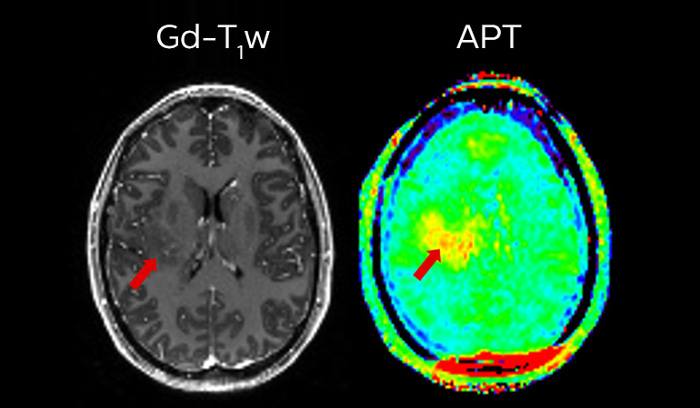

We are continuing with our partners our journey to make MR more accessible1 and definitive2. At ISMRM this year, you will see some more developments that contribute to bringing our vision to life. The need for speed for instance, with Compressed SENSE3, which relies on a heavy sub-sampled acquisition and iterative reconstruction. Come see also our advancements on APT3 (Amide Proton Transfer) a non-contrast technique based on endogenous cellular proteins in tissue, typically present in brain tumors.

APT3 - Non-Contrast technique generating MRI contrast based on endogenous cellular proteins concentration in tissue.

APT** and REACT**: The next steps towards non-invasive imaging strategies for pediatric MRI

Jeffrey H. Miller, MD

Vice Chair of Radiology for Research and Academic Affairs, Phoenix Children’s Hospital, Phoenix, AZ, USA